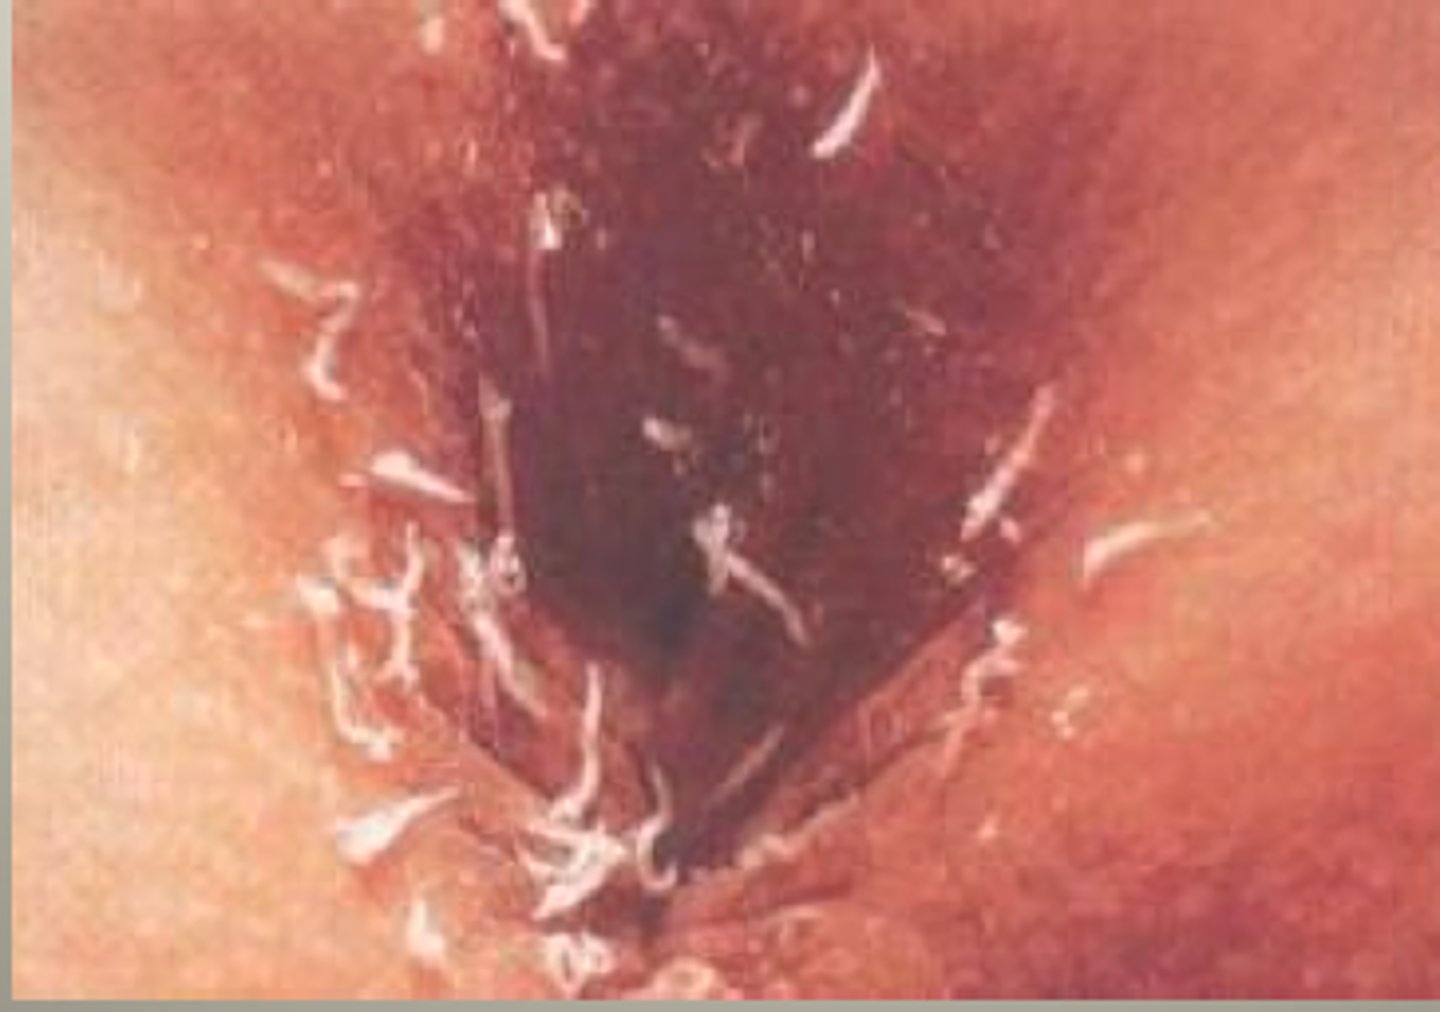

Nematode.

Round worm, example pinworm.

Tape test.

Method to diagnose pinworm by placing tape on the rectum to look for eggs/larvae.